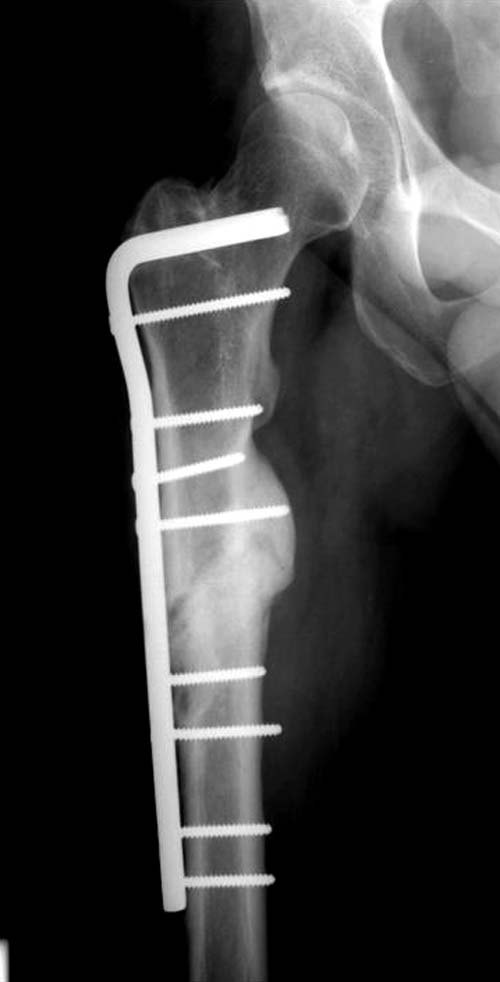

Поэтому хотел предложить альтернативную технику, открыть место ложного сустава субвастус доступом и кортикотомия, одномоментное удлинение, аппозиция латерального кортекса. Для фиксации Blade Plate с коротким клинком при возможности или обычная прямая преконтурированная 4.5 мм пластина с медиальным костным графтом.

По-моему, такая простая техника решит проблему склерозированного старого ложного сустава намного дешевле, чем гвоздь, и без необходимости обьязательного ЭОПпри установке Гамма.